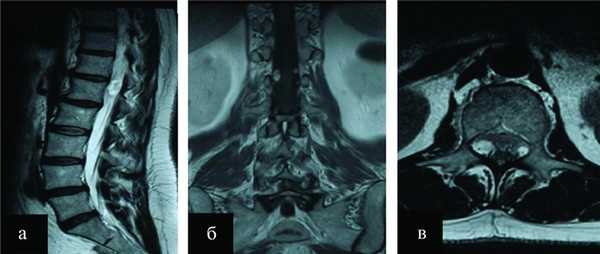

Пациентка Е., 52 лет, поступила в НИИ нейрохирургии им. акад. Н.Н. Бурденко 06.02.14 с жалобами на выраженные боли в области поясничного отдела позвоночника, боли распространялись по передней поверхности обеих ног. Из анамнеза заболевания известно, что вышеуказанные жалобы беспокоили пациентку в течение последних 2 лет. За последний год боль усилилась, стала носить постоянный характер, что послужило причиной выполнения магнитно-резонансной томографии (МРТ) поясничного отдела позвоночника в мае 2013 г. При исследовании были выявлены две интрадуральные опухоли, располагавшиеся на уровне LI позвонка в области корешков конского хвоста и конуса спинного мозга. Образования достаточно интенсивно накапливали контрастное вещество (рис. 1, б, в).

Рисунок 1. Экстрамедуллярные интрадуральные опухоли на уровне LI позвонка. а - МРТ-исследование в Т2 режиме, сагиттальная проекция; б, в - Т1 режим с контрастным усилением; б - фронтальная проекция; в - аксиальная проекция.

По рентгенологической картине опухоли соответствовали невриномам и занимали латеральное расположение с двух сторон позвоночного канала. Пациентка была консультирована нейрохирургом, но по каким-то причинам, на тот момент, от предложенного хирургического вмешательства воздержалась. В течение 1 года болевой синдром прогрессировал, появилась слабость в ногах, что и послужило причиной выполнения контрольной МРТ. По данным МРТ пояснично-крестцового отдела позвоночника (см. рис. 1), проведенного в январе 2014 г., отмечен рост интрадуральных образований. 10.02.14 произведена операция - удаление интрадуральных экстрамедуллярных опухолей на уровне ThXII-LI позвонков. Для осуществления доступа использовался реечный ранорасширитель, была выполнена традиционная ламинэктомия, частично резецированы дужки ThXII и LI позвонков. Произведен линейный разрез твердой мозговой оболочки по средней линии. С двух сторон от корешков конского хвоста, располагавшихся в центре окна ламинэктомии, визуализированы два узла опухоли. Последние располагались вдоль стенок дурального мешка и компримировали конус и корешки спинного мозга (рис. 2, а-в).